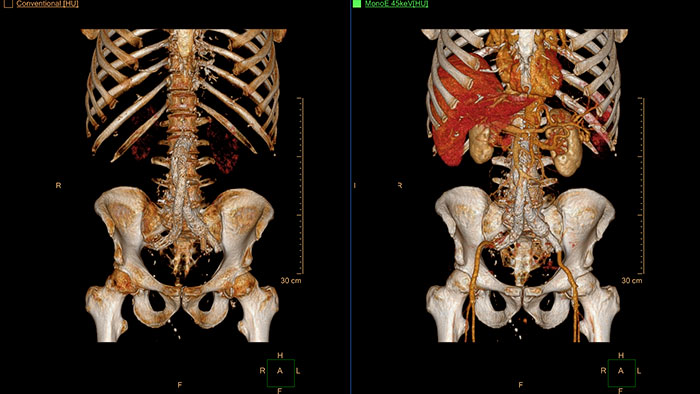

Streamlined modeling workflow

Allows to view volumetric images of anatomical structures, perform segmentation, edit and combine segmented elements (tissues) into a 3D model.

Inspection of tumors, as contrast enhanced, soft tissue oriented, and whole-body scans

Assists clinicians in viewing and evaluating CT images acquired on the IQon CT scanner for the inspection of tumors, as contrast enhanced, soft tissue oriented, and whole-body scans. It supports lesion viewing and analysis based on different spectral data types such as iodine density maps or virtual non-contrast-enhanced images.